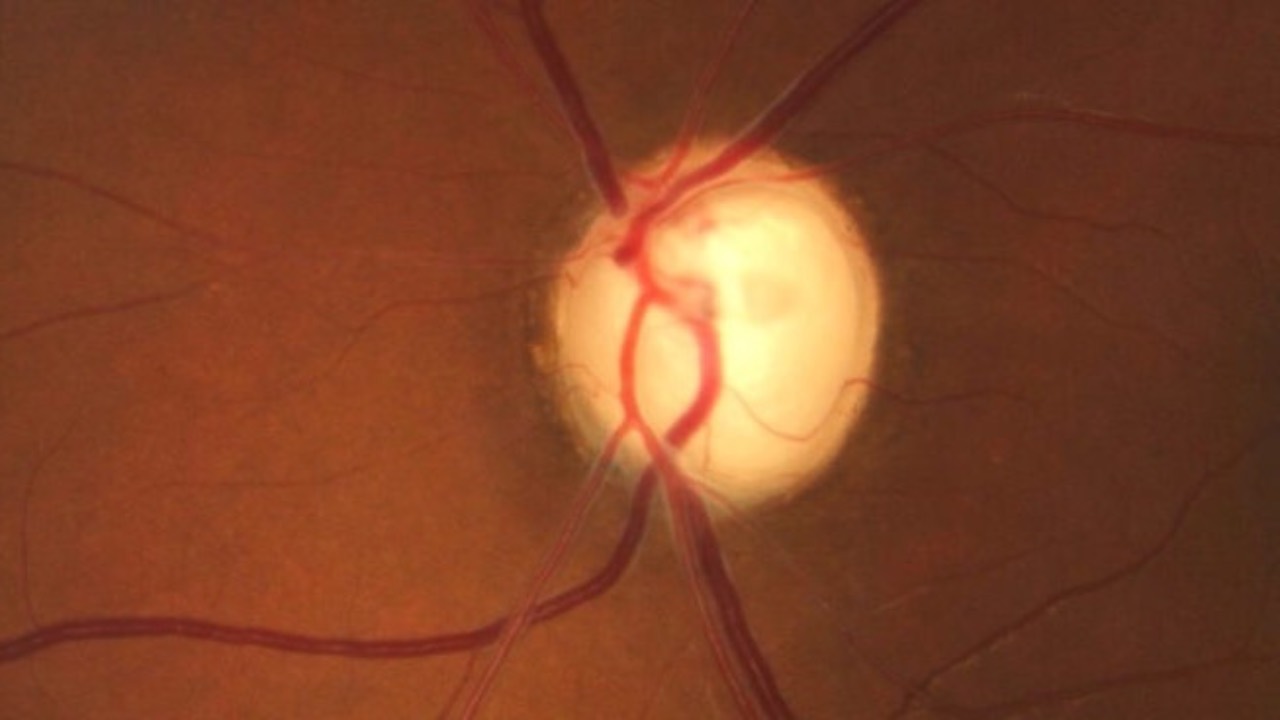

Nocturnal IOP Reduction Matters

Do you understand the dynamics?...

Nocturnal intraocular pressure (IOP) reduction is key in managing glaucoma, particulary normal tension glaucoma (NTG). There is a not too surprising link between expected elevated nocturnal IOP and glaucomatous progression, emphasizing the importance of understa...

Uveitis & Glaucoma Treatment

Do you hesitate to start that prostaglandin?...

The Sight Outcomes Research Collaborative (SOURCE) data has given us some unexpected insight on the incidence of uveitis following the start of various glaucoma medications.

In a study involving 67,517 patients, only 0.87% developed uveitis within ...